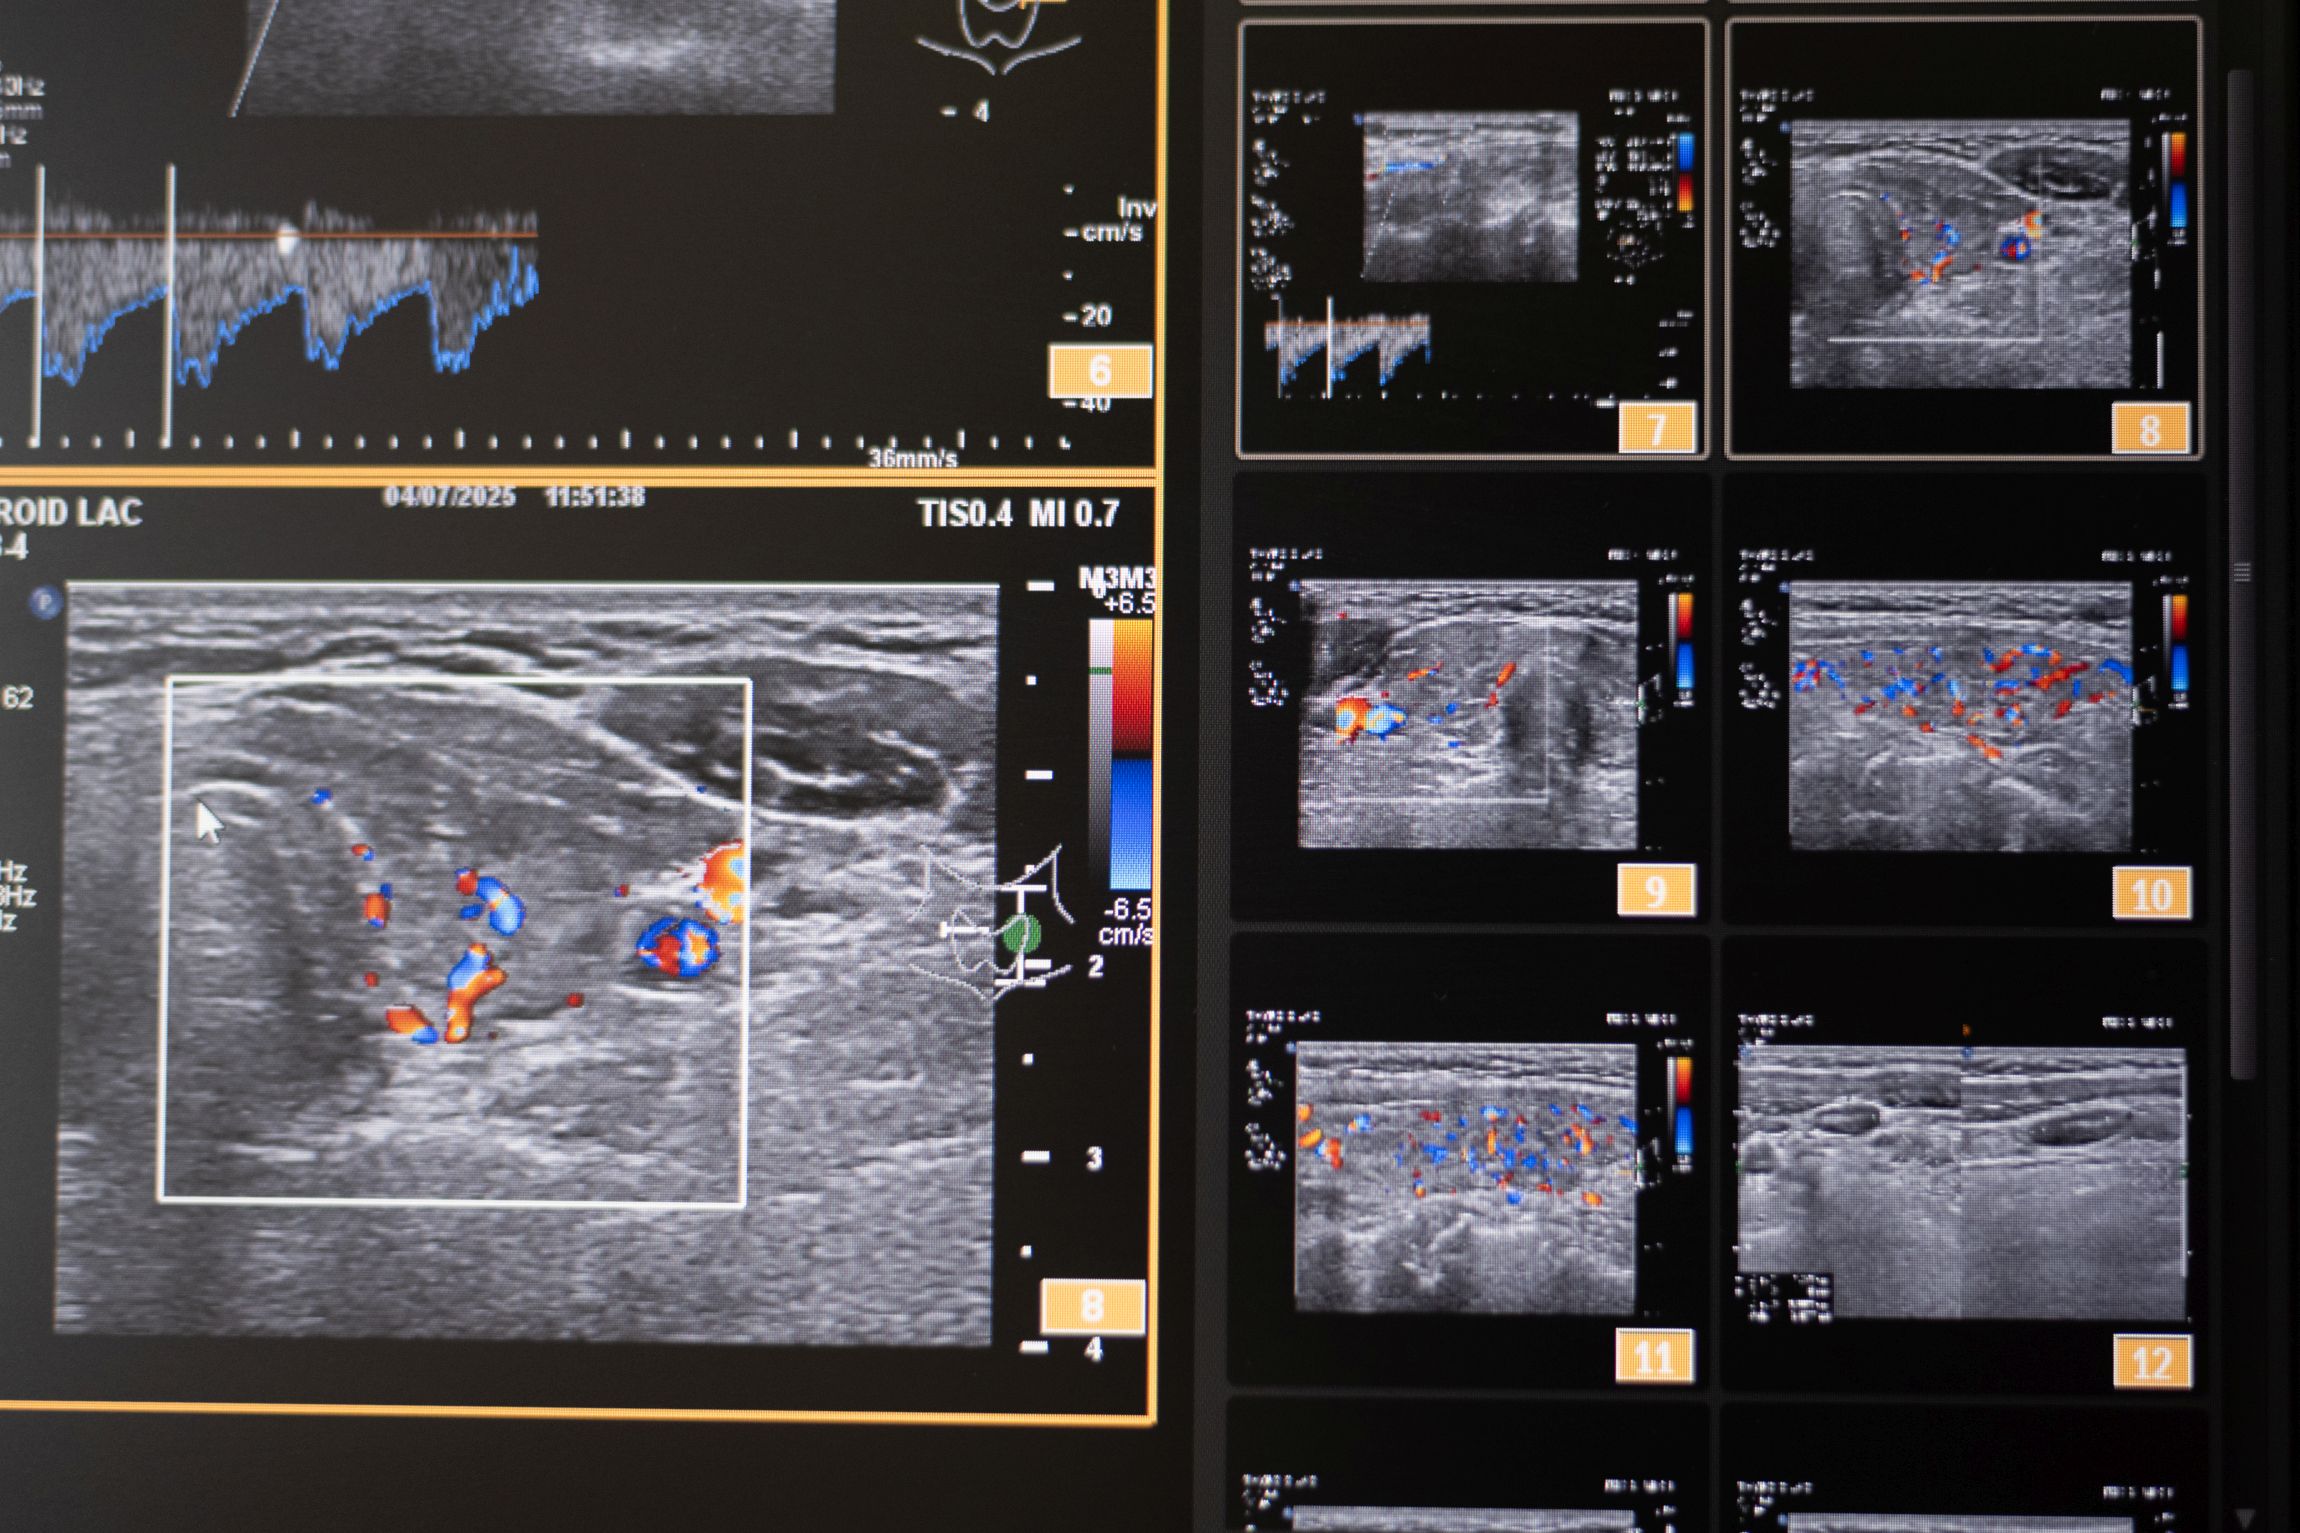

Color Doppler je temeljen na ultrazvučnoj tehnologiji koja pomoću Doppler-ovog efekta procjenjuje prokrvljenost cijele štitnjače i čvorova u štitnjači, kao i limfnih čvorova vrata. Pomoću color Dopplera računamo brzine protoka kroz krvne žile koje hrane štitnjaču, čime dobivamo važne hemodinamske parametre. Na temelju ovih pokazatelja donosimo važne dijagnostičke zaključke, te efikasno pratimo efekte liječenja štitnjače.

U sklopu Centra za štitnjaču Poliklinike Lacić nabavljen je najnoviji američki ultrazvučni aparat sa color Dopplerom Philips Affiniti 70, koji je opremljen jedinstvenim „PureWave“ ultrazvučnim sondama. Tehnologija izrade tzv. „single crystal“ ili „PureWave“ ultrazvučnih sondi omogućuje duboku penetraciju što omogućuje bolju vizualizaciju štitnjače i svih struktura vrata. Philips Affiniti 70 ultrazvučni sustav je jedini sustav u klasi koji može koristiti „single crystal“ ili „PureWave“ tehnologiju. Čisti, uniformni „PureWave“ kristali imaju 85% bolju učinkovitost prilikom emitiranja i primanja ultrazvučnih zraka nego klasični piezoelektrični materijali. Ova izuzetna tehnologija omogućuje naprednu penetraciju uz izvrsnu rezoluciju u dubljim dijelovima slike, čime se postiže vrhunski prikaz štitnjače i svih struktura vrata. Time se omogućuje još točnije mjerenje svih morfoloških kao i hemodinamskih parametara. Na taj način smo u mogućnosti još ranije otkrivati bolesti štitnjače a samim time ih onda i bolje liječiti.